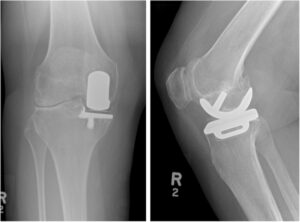

Requisiti radiografici e di imaging

Radiografie in carico: evidenza di degenerazione severa nel compartimento target e conservazione ragionevole degli altri compartimenti.

Deformità correggibile (varo per UKA mediale; valgo per UKA laterale) e non rigidamente strutturata.

Patello-femorale: assenza di coinvolgimento severo sintomatico; la PF lieve-moderata può essere compatibile in casi selezionati, ma la PF avanzata con dolore anteriore dominante pesa contro l’UKA.

Valutazione asse (long-leg) consigliata quando deformità clinica rilevante, per evitare overcorrection e accelerazione della progressione controlaterale (problema classicissimo)

- Radiografie in carico: AP/LAT, Rosenberg o proiezioni in flessione per compartimento, assiale rotula

- Valutazione asse meccanico (long-leg) in caso di deformità

- RX in carico conferma OA severa confinata

- Compartimento controlaterale conservato

- PF non severa sintomatica dominante